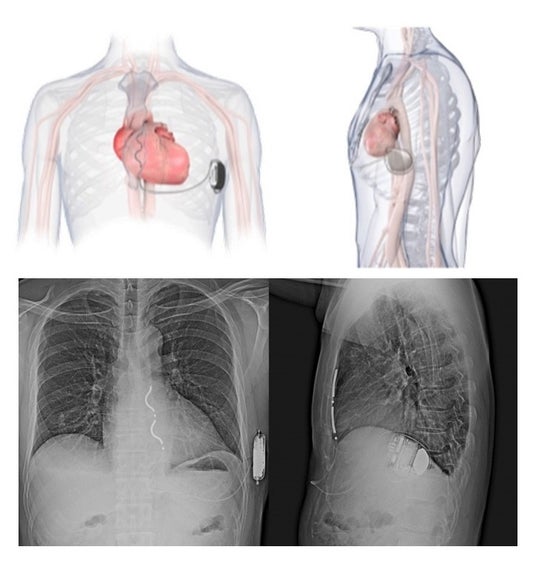

上図:デバイス植え込みのイメージ図。本体は心尖部と中腋窩線が交わるところに植え込まれ、リードはみぞおちから胸骨下の縦隔内に植え込まれる。下図:デバイス植込み後の胸部X線画像。

心臓の頻脈性不整脈の治療には、従来から、リード(導線)を、血管を通して心臓内に固定する経静脈的「植込み型除細動器(ICD)」が使用されてきましたが、体内への留置年数が長期間になると、リードの断線や血管閉塞、感染などのトラブルが発生するリスクが問題になっていました。今回保険適用になったEV-ICDは、リードが心臓の近くで血管の外側に留置されるため不整脈を感知しやすく、血流感染などのリスクも低減されます。